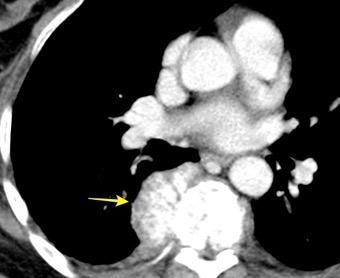

32 años .Preeclampsia a los 19. Hipertensión no controlada. Masa paravertebral sólida que se realza intensamente con afectación ósea.

Yue Y t al. Asymptomatic left posterior mediastinal functional Paraganglioma. A case report. Medicine . 2019